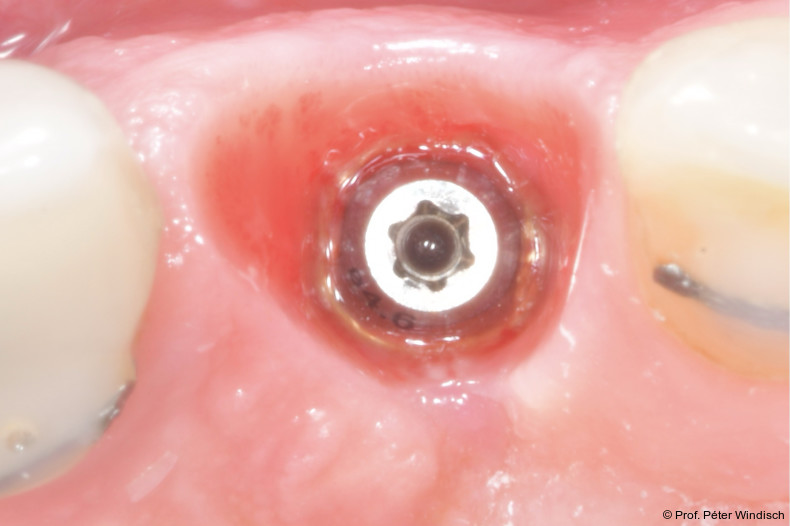

Radiologisch war ein signifikanter Knochenabbau um das Implantat zu verzeichnen (Abb. 2). Die klinische Untersuchung zeigte klassische Anzeichen einer periimplantären Entzündung: Bluten auf Sondieren (BOP+), erhöhte Sondierungstiefen (ST) und eine lokale Schwellung der Mukosa (Abb. 3–5). Das primäre Ziel war es, den Entzündungsprozess nicht chirurgisch zu stoppen und ein biologisches Milieu zu schaffen, das eine langfristige Stabilität ermöglicht. Der Implantataufbau wurde derzeit am Halsbereich zu dick ausgearbeitet und wies aus diesem Grund kein optimales Emergenzprofil auf. Nach der Eingliederung der definitiven prothetischen Versorgung kann es – insbesondere bei dicken suprakrestalen Weichgeweben – vorkommen, dass sich das Weichgewebe an die Kronenkontur adaptiert, was biologisch nicht immer gut toleriert wird. In der Folge kann es zu einer lokalen entzündlichen Reaktion kommen. Aus diesem Grund war zudem eine Umgestaltung der Krone vorgesehen.

Die erste Säule der Behandlung („Clean“-Phase) bildete die submarginale Instrumentierung unterstützt durch das Reinigungsgel. Da eine rein mechanische Reinigung oft nicht ausreicht, um den Biofilm in den Mikrostrukturen der Implantatoberfläche vollständig zu entfernen, wurde nach dem Entfernen der Krone adjuvant das Reinigungsgel (Perisolv) eingesetzt.

Nach einer Einwirkzeit von mindestens 60 Sekunden (Abb. 6) wurde die Tasche und die Implantatoberfläche gründlich mit Titanküretten instrumentiert. Während der Instrumentierung wurde das Reinigungsgel mehrmals in die Tasche appliziert und 60 Sekunden einwirken gelassen (ca. fünf bis sechs Mal), jeweils gefolgt von weiteren Instrumentierungszyklen. Dies wurde so oft wiederholt, bis keine sichtbaren Konkremente mehr aus der Tasche kamen (Abb. 7).